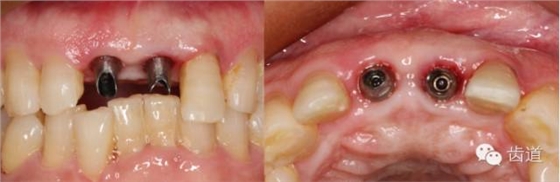

植入種植體(唇側(cè)留2-3mm jumping gap)

確定植入深度(齦下3-4mm)

戴牙(基臺(tái)就位)

戴牙